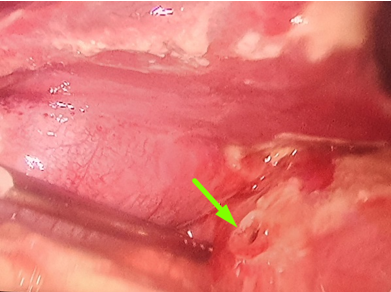

Ảnh thủng mặt trước hành tá tràng quan sát trong mổ của bệnh nhân Đ (mũi tên xanh) |

Ảnh thủng mặt trước hành tá tràng quan sát trong mổ của bệnh nhân Đ (mũi tên xanh)